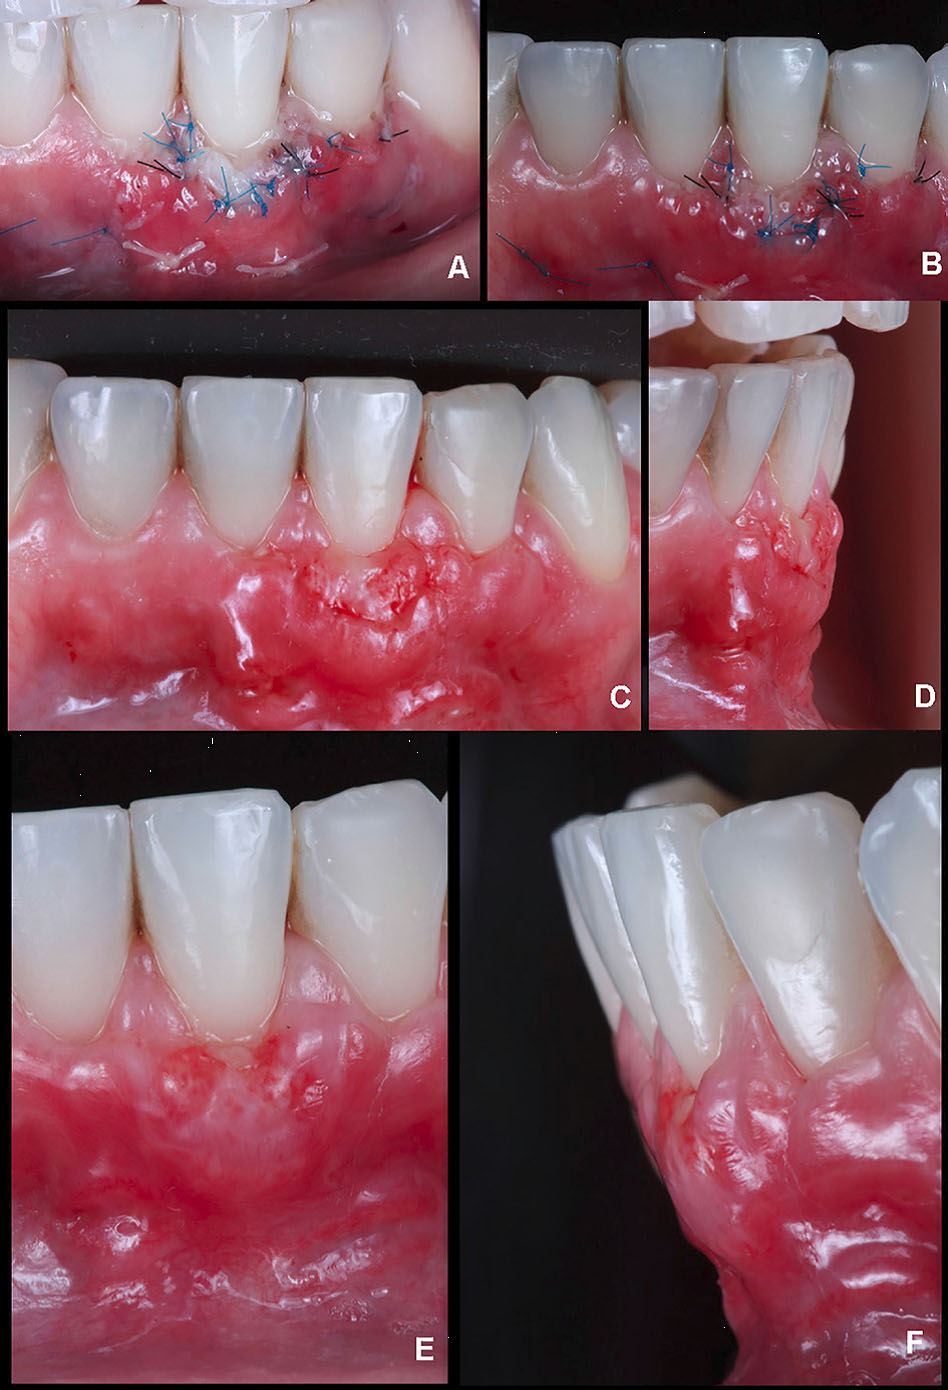

Within nine days, a high level of vascularization and integration of the soft tissue graft was verified, reducing the white layer and maintaining the volume. Nevertheless, there was a reduction of tissue height in the facial zone (Figure 4E, F) compared to the outcome at six days. After 11 (Figure 5A, B) and 13 days (Figure 5C, D), improved healing was found with slight differences between them. In 16 days (Figure 5E), it was possible to report stable tissues, confirmed after 31 days (Figure 5F, G), with a significant GR reduction and increased KTW and GT. Moreover, it improved the PES analysis score from 5 (day 0) to 9 (31 days).

Figure 5.

A and B. Eleven days after the procedure, C and D. Thirteen days after surgery. Volume was maintained, but a slight recession could be observed. E. After 16 days, the tissues stabilized. F and G. After 31 days; stable tissues, with normal coloration and exciting volume.